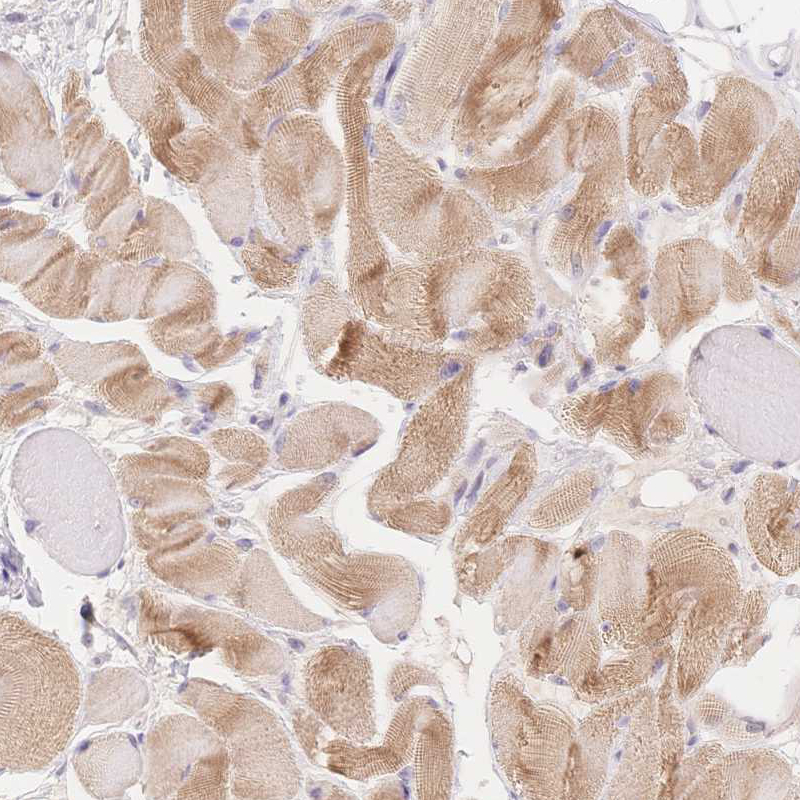

Immunohistochemistry analysis in human heart muscle and pancreas tissues using HPA049193 antibody. Corresponding MYOM1 RNA-seq data are presented for the same tissues.